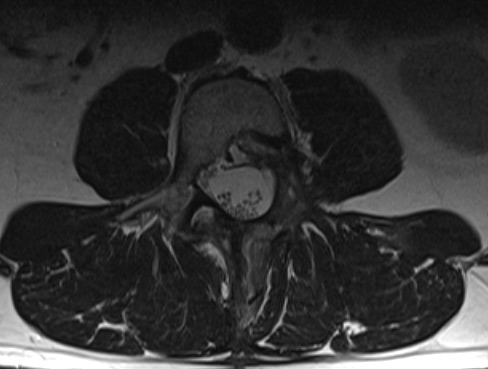

Paciente de 52 años que refiere lumbalgia inespecífica con irradiación ocasional en muslo (justo arriba de la rodilla) derecha. Sin focalidad.

Imagen con gadolinio, distribución homogénea, bordes definidos; la resolución ósea no significa malignidad en estos tumores; la ocupación de canal >50% tampoco significa que sean intradurales subaracnoideos

Craneal es izquierda; medial es inferior.